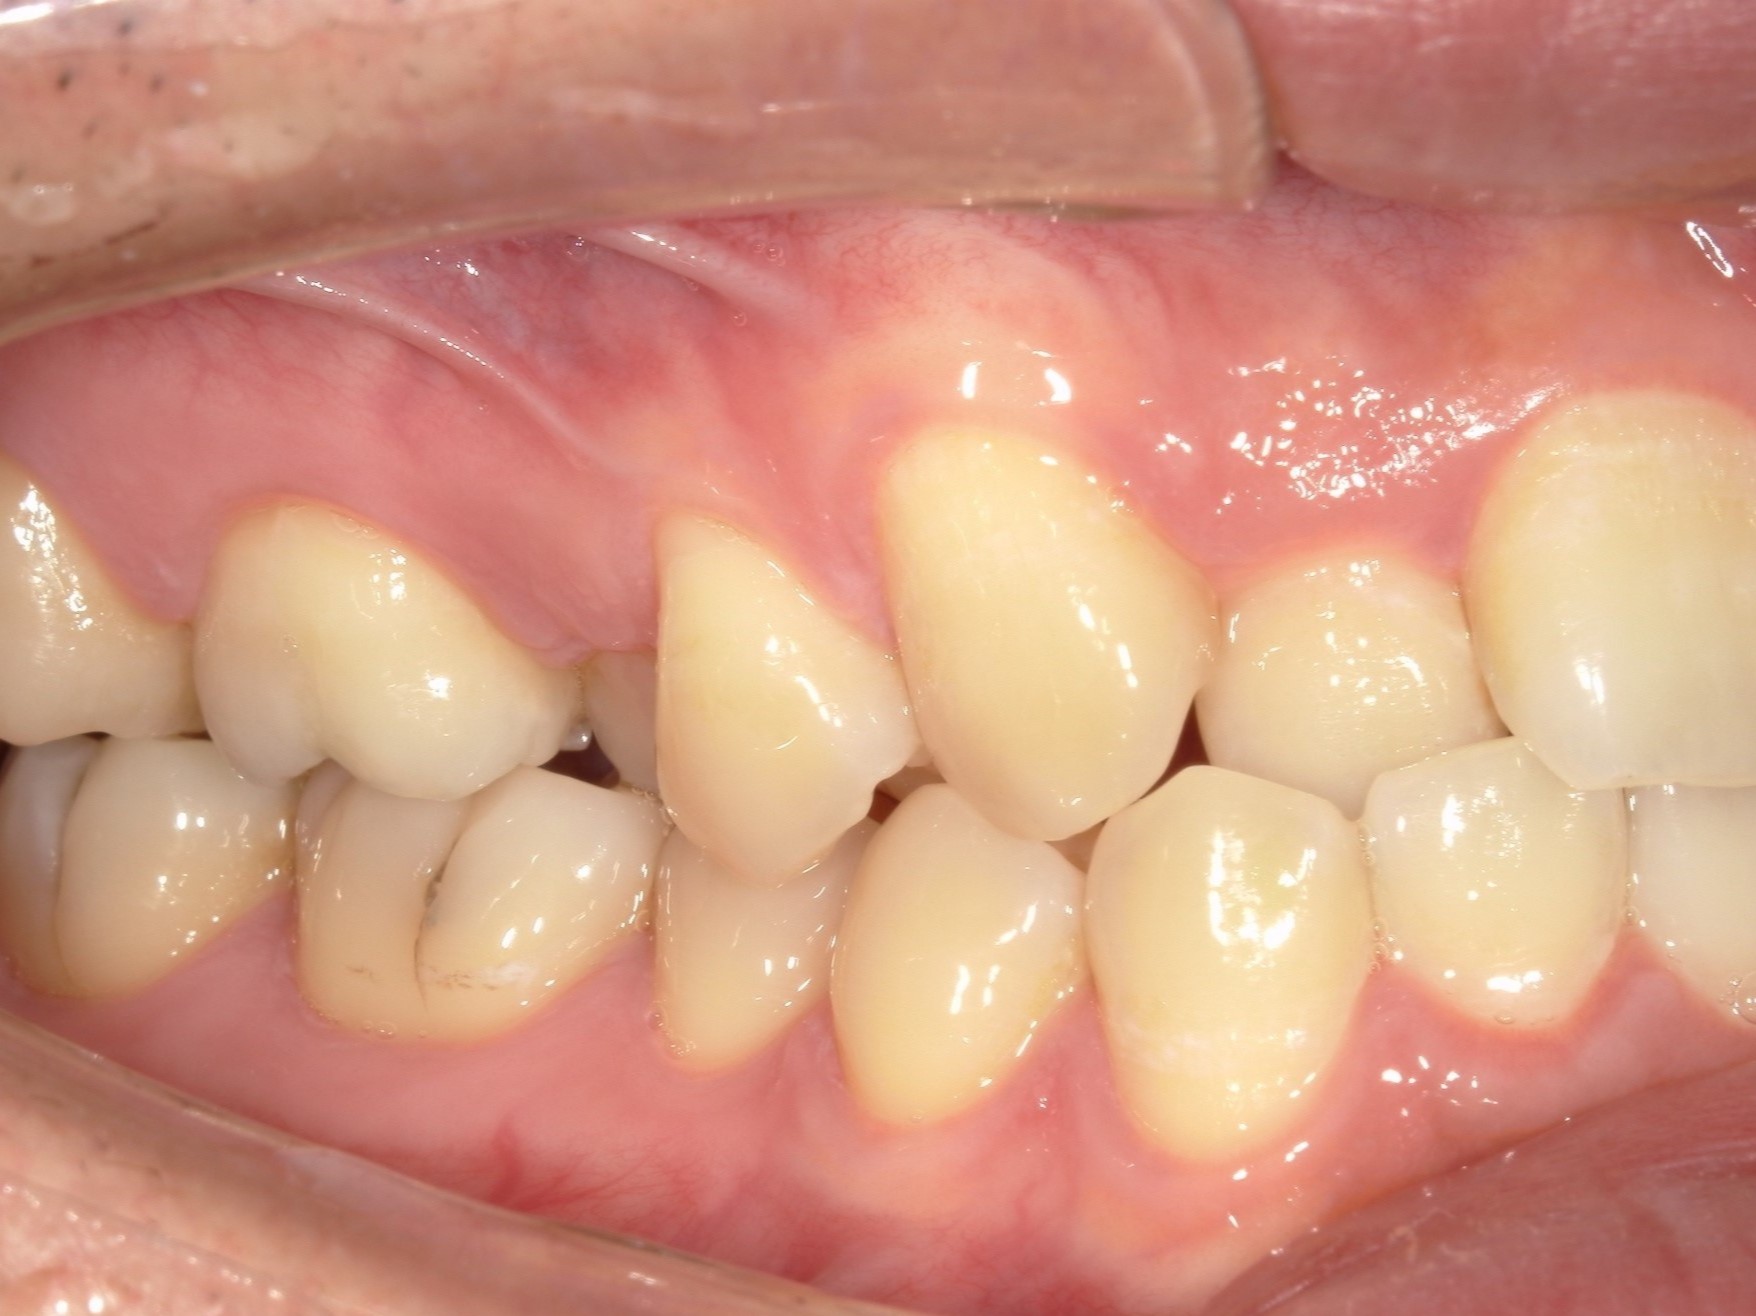

20代男性の方で、叢生・全体的な歯並び(不揃い・ガタガタ・不正咬合)が気になる患者様です。

歯が重なり合う状態は、見た目の問題だけではなく歯磨きが難しくなり虫歯や歯周病を引き起こすリスクにもなるため、インビザライン(重程度)矯正を行いました。

治療期間は約1年半、枚数は89枚です。

治療内容 歯が重なり合う状態は、見た目の問題だけではなく歯磨きが難しくなり虫歯や歯周病を引き起こすリスクにもなるため、インビザライン(重程度)矯正を行いました。

左右の下顎智歯(親知らず)抜歯をしました。